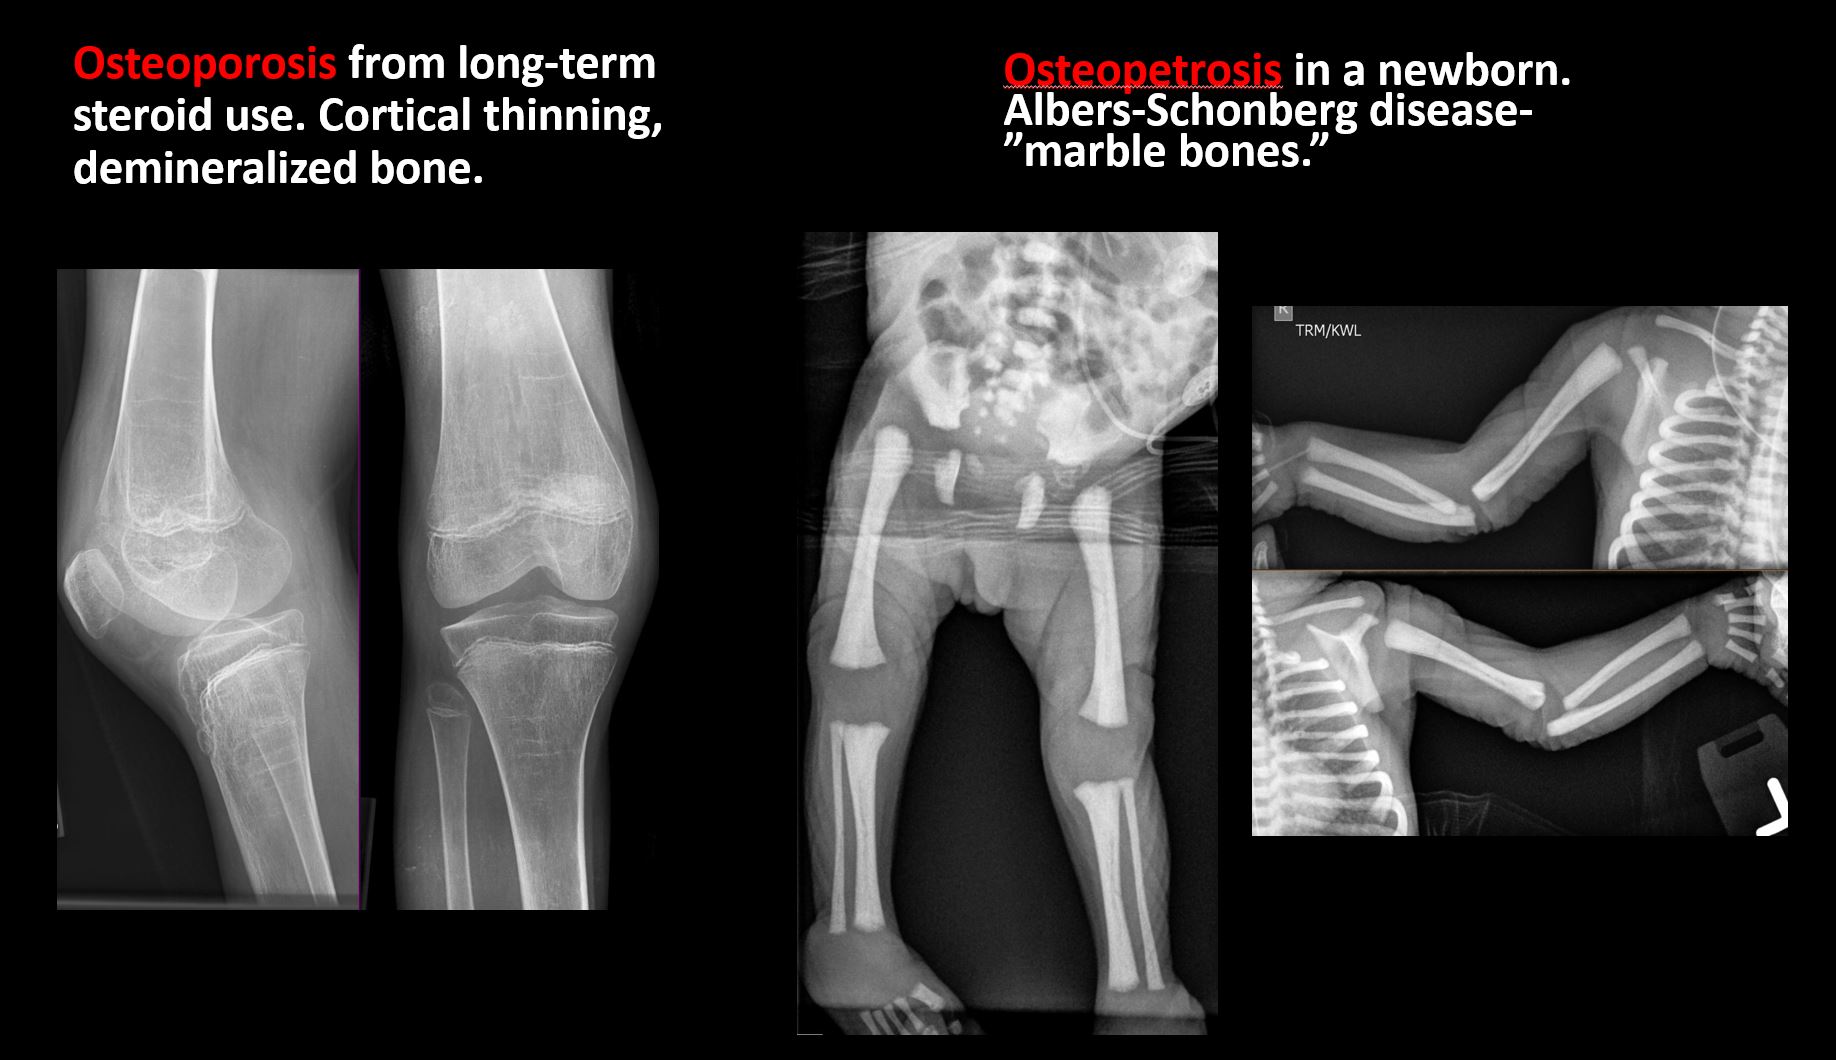

Overall bone density is increased or decreased with or without thinning or thickening of the cortical or cancellous bone. |

No | NA |